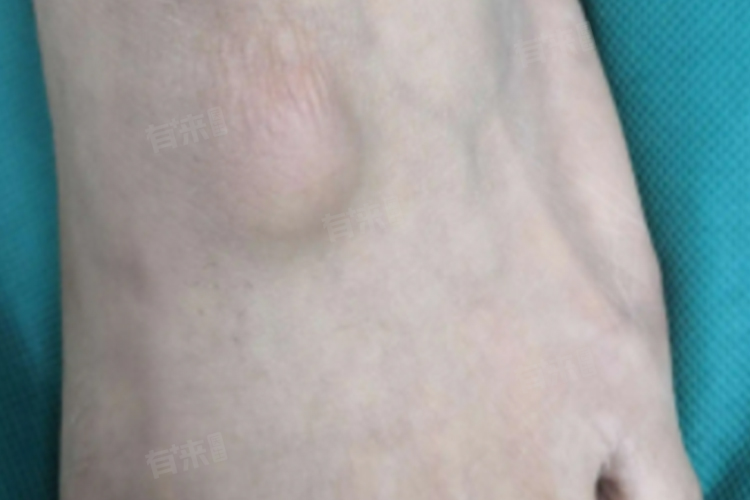

5、腱鞘囊肿:

- 由于肌腱在腱鞘内反复摩擦所致,常见于经常走路或穿鞋较小的人,鞋面较小与足背肌腱摩擦形成囊肿,有时可伴随局部疼痛、活动受阻等症状。

- 肿块一般呈圆形,大小不一,表面光滑,与皮肤无粘连,基底固定,无压痛感。局部封闭适用于早期腱鞘囊肿,必要时可手术治疗。手术通常在专业医生操作下,通过切除腱鞘囊肿并加强缝合深部的关节囊组织,尽量避免囊肿的复发。